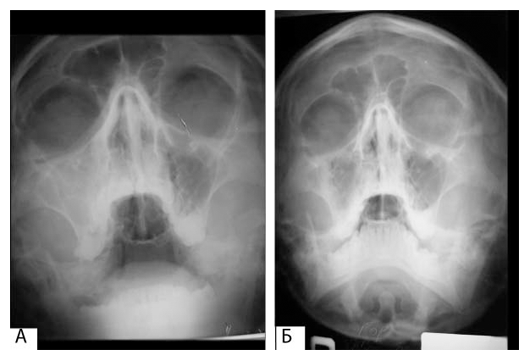

Рис. 1. Рентгенограмма в носолобной проекции:

А) до операции, Б) через 3 месяца после операции

Больной Г. 20 лет, обратился в клинику с жалобами на наличие сообщения полости рта и носа после удаления 16-ого зуба 3 месяца назад. При объективном осмотре больного со стороны внутренних органов отклонений от нормы не выявлено. При осмотре полости рта выявлен свищевой ход в области лунки 16-ого зуба, через который ротовая полость сообщалась с гайморовой пазухой (рис 3.1). Выделение гноя из носа со стороны гайморовой пазухи не определялось. На рентгенограмме в носолобной проекции вы-являлось правостороннее затемнение ВЧП (рис 1А). На внутриротовой рентгенограмме альвеолярного отростка верхней челюсти справа лунка 16-ого зуба сообщается с ВЧП (рис 2а). На основании клиникорентгенологических исследований диагностирован правосторонний перфоративный гайморит. Под общим обезболиванием произведена радикальная опера-ция ВЧП, с пластическим закрытием ороантрального сообщения. Предварительно освежали края лунки 16-ого зуба, затем проводили радикальную гайморотомию.

Контрольный осмотр больного Г. произведен через 3 месяца. Больной жалоб не предъявляет. Открывание рта свободное, слизистая оболочка преддверия полости рта по проекции удаленного зуба без особенностей, прослеживается тонкий послеоперационный рубец (рис 4). Пальпация безболезненна. На внутриротовой рентгенограмме в области лунки 16-ого зуба прослеживается новообразованная органотипичная костная ткань (рис 2.б). На рентгенограмме, произведенной в носолобной проекции, прозрачность правой ВЧП почти идентична с левой (рис 1Б). Интерес данного случая заключается в успешном пластическом закрытии ороантрального сообщения по предлагаемому нами способу.